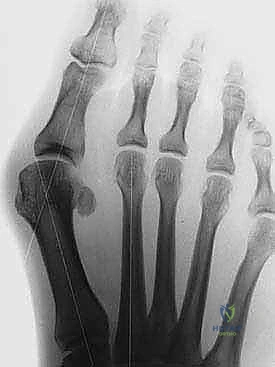

- التصوير بالأشعة السينية (X-rays) أثناء الوقوف: هذا أمر بالغ الأهمية. الأشعة والوزن محمل على القدم تظهر الدرجة الحقيقية للتشوه.

يقوم الدكتور هطيف بقياس زوايا محددة:

* زاوية إبهام القدم الأروح (HVA): الزاوية بين عظم المشط الأول والإصبع الكبير.

* الزاوية بين الأمشاط (IMA): الزاوية بين عظم المشط الأول والثاني.

بناءً على هذه الزوايا، يتم تصنيف الحالة إلى خفيفة، متوسطة، أو شديدة. جراحة (ماو) تُخصص عادة للحالات المتوسطة إلى الشديدة التي تتطلب تصحيحاً كبيراً ومستقراً.

بعد قص العظم، يتم تحريك الجزء البعيد (الذي يحمل المفصل والإصبع) نحو الخارج لتصحيح التشوه وتضييق المسافة بين الأمشاط. بمجرد الوصول للوضع المثالي، يتم تثبيت العظمين معاً بقوة باستخدام برغيين أو ثلاثة من التيتانيوم الطبي عالي الجودة. هذه البراغي تدفن داخل العظم ولا تحتاج للإزالة لاحقاً.

بعد التأكد من استقرار العظم ووضعه المثالي (غالباً باستخدام جهاز أشعة سينية داخل غرف العمليات Fluoroscopy)، يتم إزالة النتوء العظمي المتبقي. أخيراً، تُغلق الكبسولة المفصلية والجلد بخياطة تجميلية دقيقة لتقليل الندبات، وتوضع ضمادات ضاغطة خاصة.